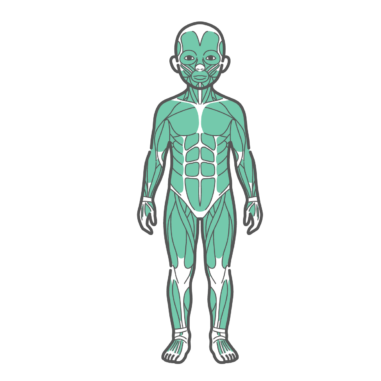

上半身・体幹 男の子(子供)の全身筋肉図・人体解剖図のイラスト(正面・前面)